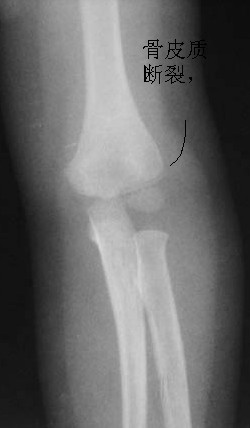

男儿,5岁,左肘部外伤,局部肿胀一天。

左肱骨小头上方骨皮质不连续,隐示一';线';型骨折线,软组织肿胀,考虑左肱骨小头骨骺分离

左肱骨小头[肱骨小头位于前线之前,9岁以下应该位于前线之后]上方骨皮质不连续,隐示一';线';型骨折线,软组织肿胀,考虑左肱骨小头骨骺分离。

表现:正位肱骨远侧干骺端可见横行低密度线延伸至外髁,外髁皮质断裂,侧位前侧骨皮质也有断裂。对侧好像有类似之处,但那是与肱骨小头骨骺的重叠影。

印象:肱骨低位髁上骨折